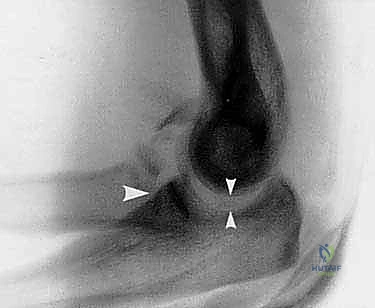

2. التصوير بالأشعة السينية (X-Rays)

يتم إجراء صور أشعة سينية من زوايا متعددة (أمامية خلفية، وجانبية). الأشعة السينية تؤكد وجود الخلع وتظهر الكسور الواضحة في رأس الكعبرة والناتئ الإكليلي. في قسم الطوارئ، غالباً ما يتم إجراء "رد مغلق" (إعادة العظام إلى مكانها يدوياً تحت التخدير) ثم وضع جبيرة مؤقتة، وإعادة التصوير بالأشعة للتأكد من نجاح الرد المبدئي.

3. التصوير المقطعي المحوسب (CT Scan) - الخطوة الذهبية

لا يمكن التخطيط لجراحة الثالوث الرهيب بنجاح دون إجراء أشعة مقطعية.

الصور المقطعية، خاصة تلك التي تتضمن إعادة بناء ثلاثية الأبعاد (3D Reconstruction)، توفر للدكتور هطيف خريطة دقيقة للإصابة. تكمن أهمية الأشعة المقطعية في:

* تحديد حجم وشكل كسر الناتئ الإكليلي بدقة (هل هو مجرد قشرة عظمية أم كسر كبير يشمل القاعدة؟).

* تقييم مدى تفتت كسر رأس الكعبرة (هل يمكن تثبيته بمسامير أم يحتاج إلى استبدال بمفصل صناعي؟).

* اكتشاف أي شظايا عظمية صغيرة محشورة داخل المفصل قد تعيق حركته.